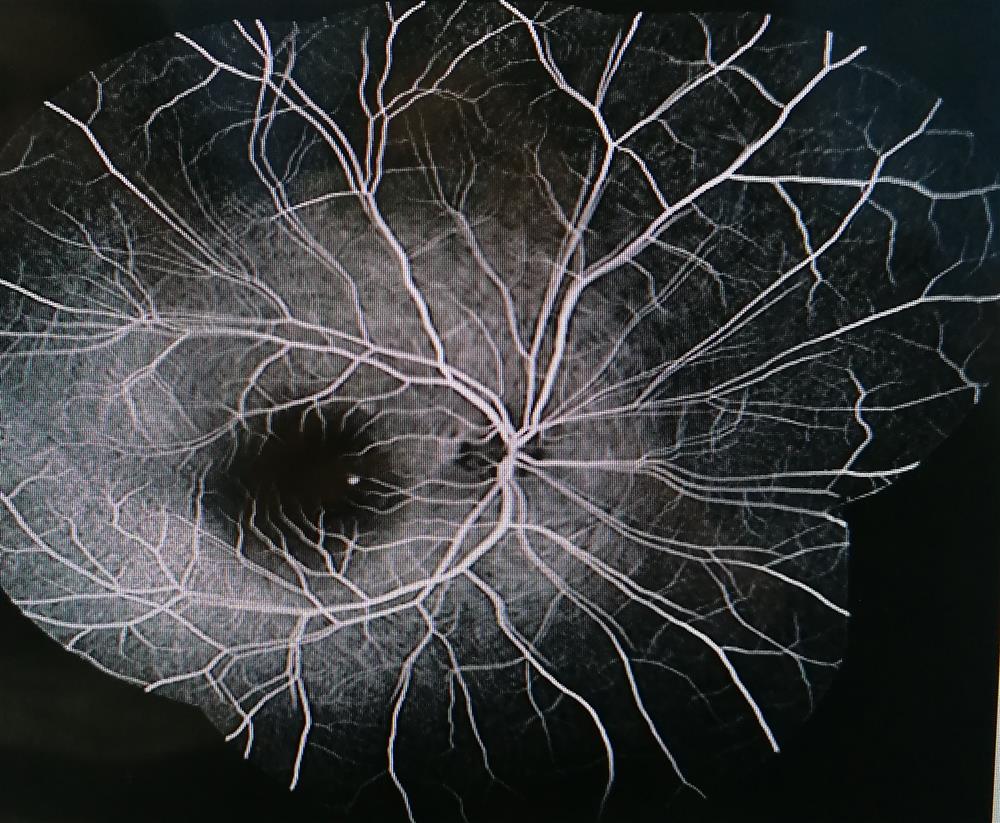

The entire angiography procedure takes less than half an hour. First, pupil-dilating drops are placed in the patient's eyes. After the pupils dilate, a harmless dye called fluorescein is injected into the arm vein. In the first 10 to 15 seconds after injection, the fluorescein dye travels throughout the body's blood vessels and reaches the retinal vessels, causing them to glow.

When the fluorescent dye reaches the retinal vessels, a special camera takes pictures of them. These images help the doctor identify retinal abnormalities and target areas for treatment.